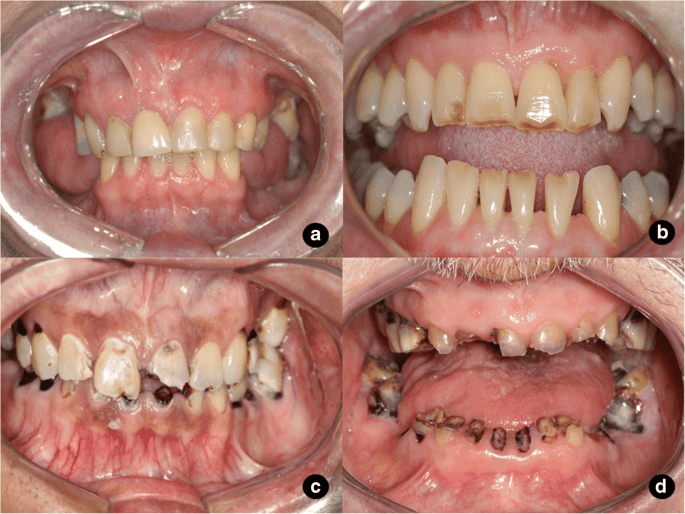

In a healthy mouth, saliva balances the acidity of the mouth and helps digest any sugars eaten. Radiation therapy usually decreases saliva production, which can result in an increased risk of tooth decay, cavities, gum disease, jawbone destruction, and infection.

When cancer treatment is not urgent, patients should visit a dentist at least four weeks before treatment begins. Oral examination before cancer treatment can identify problems like dental cavities, fractured teeth, gum disease and all these problems need to be addressed to reduce the risk of side effects after cancer treatment.

Cancer treatment can lower the body’s immune system. Which makes it easy for bacteria to spread. As dental cavities and gum disease are caused by bacterial infections. Before cancer treatment to reduce the risk of bacterial infection in other parts of the body. They should be treated during and after. If dental problems are treated before cancer treatment begins. So the severity of oral diseases can be reduced.

Radiotherapy reduces the blood supply to your jawbone and therefore reduces the bone’s ability to heal. This means, if you need to have a tooth extracted after radiotherapy. So there is a possibility that the bone associated with the tooth may die. This leads to a painful condition called osteoradionecrosis.